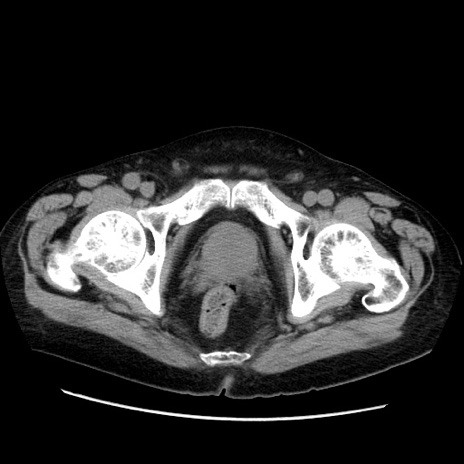

症例21(横断像)

【症例】70歳代男性

【主訴】腹痛

【現病歴】肝硬変・肝細胞癌にてかかりつけの方。約9時間前に食後より腹痛出現。症状が徐々に増悪し、嘔吐出現したため来院。

【既往歴】肝硬変、肝細胞癌(RFA、TACE後)

【身体所見】意識清明、表情苦悶様、BT 36℃、BP 129/78mmHg、P 88bpm、SpO2 97%(RA)、右上腹部から心窩部にかけて圧痛あり、反跳痛なし、筋性防御あり。

【データ】WBC 5800、CRP 0.16